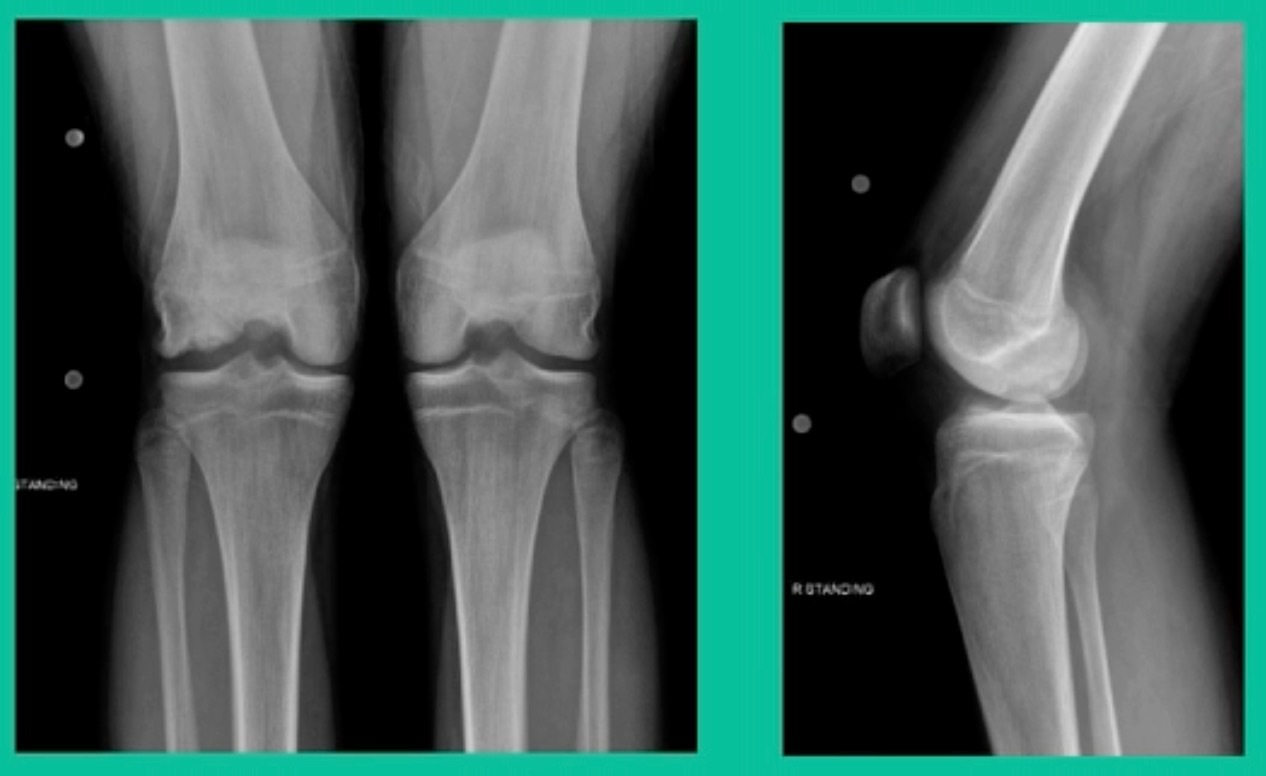

Now, we’ll shift to the adult. This is a 27-year-old. Right knee swelling, activity-related, and classic failed nonsurgical treatment on the lateral side of the knee.

This will probably be fixed. It’s a big piece and we’ll try to preserve it. The literature shows that preservation does pretty well. In this instance, there’s very little bone. It’s somewhat dystrophic, not very encouraging in my mind.

We removed it, and you say, “Well, this is terrible.” Lateral side, how is he going to do? Interestingly, the natural history does not suggest that that person will do badly. Probably the worst ones are going to be the ones who fall off to the side into the trochlea and lateral meniscus.